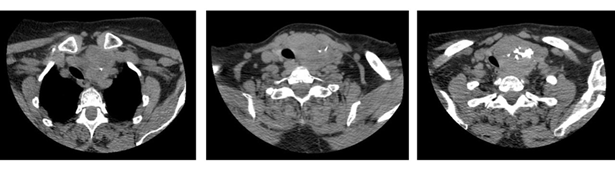

The ct of the neck reported: multinodular goiter with intrathoracic extension from the operculum 19 mm, volume 71 cc. Visceral axis of the neck well centered. No alterations are observed in the walls of the pharynx. Fatty spaces for pharyngeal muscles preserved

(figure 6).

Figure 6: ct with goiter that maintains undamaged tracheal lumen.